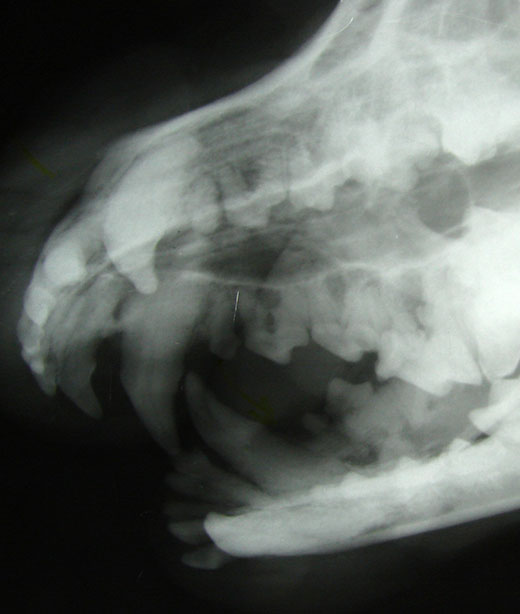

In addition to routine cleanings, Woodland Springs Veterinary Hospital offers advanced dental services such as dental x-rays. These x-rays are crucial for detecting problems that are not visible to the naked eye, including tooth root abscesses, fractures, and periodontal disease. By identifying these issues early, we can provide targeted treatments that help prevent more severe health problems down the line.